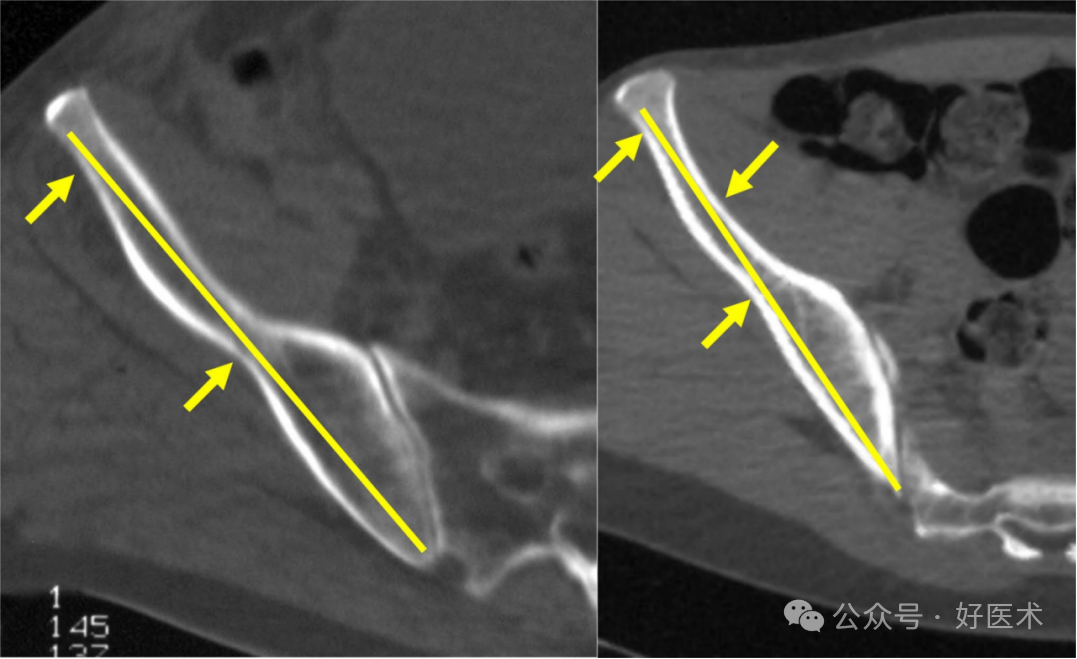

Schildhauer定义了髋臼上缘通道(SAC)的整体路径和两个狭窄区域。在男性患者中,从骶骨后上棘(PSIS)到髂前下棘(AIIS)的平均长度为141.1毫米,而在女性患者中为128.7毫米。Pichler等人报告了类似的长度,为148毫米,而De Bondt等人发现性别之间没有显著差异(男性140毫米对比女性145毫米)。男性患者的 PIIS-AIIS 长度平均为 86.3 毫米,女性患者的 PIIS-AIIS 长度平均为 99.7 毫米。该通道内存在两个狭窄区域(图18)。

图18 髋臼上通道(SAC)在轴位CT扫描中的狭窄区域。

从后部开始到**个狭窄区域的距离,男性约为 3 厘米,女性约为 2.7 厘米。在上方通路(PSIS-AIIS),男性到第二个狭窄区域的距离为86.3mm,女性为84.1mm;在下方通路(PIIS-AIIS),男性为60.3mm,女性为52.8mm。因此,在这个通道中使用长螺钉进行三点稳定是可能的。髋臼上缘通道(SAC)的平均直径在男性中为8.3毫米,在女性中为6.2毫米。这种差异是由于女性的髂骨更呈S形。一种更大的替代髋臼上缘通道在男性中测量为11.3毫米,在女性中为9.9毫米。这种替代髋臼上缘通道的起始点更靠下(位于髂前下棘AIIS的下方),出口点位于骶骨后上棘(PSIS)的前方,导致其角度更偏向头侧(图19)。这种替代髋臼上缘通道(SAC)存在进入关节内的风险,因为髋关节囊附着点可延伸至髋臼缘上方1.6厘米处。